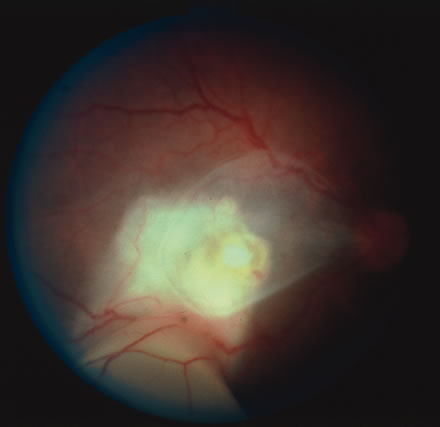

Diagnosis of varicella is usually not difficult, given the frequently obtainable history of exposure to a preexisting case and the characteristic rash. Serologic confirmation can be obtained by demonstrating increasing anti-VZV antibody titers. Multinucleated giant cells and eosinophilic intranuclear inclusions can be demonstrated by Papanicolaou's or other stains of smears from acute skin lesions. The clinical diagnosis of herpes zoster can be made in the presence of the characteristic vesicular lesions in a dermatomal distribution. Scrapings of the lesions demonstrate giant cells and intracellular inclusions. It is important to note that although most patients with herpes zoster are otherwise healthy, the possibility of an underlying systemic illness should be considered if the patient is young (i.e., younger than 50 years old) or the history suggests other systemic problems. The treatment of varicella is primarily supportive, consisting of analgesia, antipyretics, antipruritics, and good skin hygiene to prevent secondary infection. The use of aspirin in children is to be avoided in view of the belief that it may predispose to Reye's syndrome following varicella. Most eye disease is mild and self-limited and does not require treatment. Oral acyclovir (Zovirax) given five times daily early in the course of zoster infection has been shown to reduce the duration of viral shedding and the severity of acute pain. The greatest benefit is seen when medication is begun within 72 hours of onset of skin lesions. Two newer antiviral agents available for the treatment of herpes zoster are valacyclovir (Valtrex) and famcyclovir (Famvir). These agents have the advantage of a simpler dosing regimen, three times daily rather than five times daily with acyclovir, and a more favorable pharmacokinetic profile.13 It is thought that famcyclovir may also help speed resolution of postherpetic neuralgia. Valacyclvoir and famcyclovir are now preferred to acyclovir as first-line therapy for the treatment of zoster. They are well-tolerated drugs with few systemic side effects other than a requirement for reduced dosing in patients with renal failure. Oral corticosteroids also seem to have a beneficial effect in reducing acute pain and speeding cutaneous healing. They have not been shown to have an effect on postherpetic neuralgia. Topical corticosteroids and cycloplegics are commonly used to treat the inflammation associated with herpes zoster ophthalmicus.10 Tear supplements, bandage contact lenses, surgical correction of lid abnormalities, and tarsorrhaphy may be necessary to promote the healing of epithelial defects. Vision-threatening pathologic processes such as chorioretinitis and optic neuritis should be treated aggressively with intravenous acyclovir and high doses of prednisone. Treatment of postherpetic neuralgia is often disappointing. Routine analgesic drugs are generally ineffective. Cimetidine, colchicine, phenothiazines, and tricyclic antidepressants have been used with some success. Capsaicin cream and lidocaine patches may also be applied for local relief. The pain tends to slowly diminish and disappear over the course of 1 to 2 years but may be prolonged, especially in elderly patients. For those with severe intractable pain, intrathecal injection of methylprednisolone acetate once weekly for 4 weeks has recently been shown to provide relief.14 CYTOMEGALOVIRUS INFECTION Cytomegalovirus (CMV) is a herpes virus responsible for severe congenital malformations, a mononucleosis syndrome in young adults, and disseminated lesions in the immunosuppressed, especially retinal infection and pneumonia in patients with acquired immunodeficiency syndrome (AIDS). Patients with AIDS with CD4 counts between 50 to 100 cells per microliter are particularly susceptible to CMV retinitis. If the retinitis is untreated the prognosis is very poor often resulting in full-thickness retinal necrosis and blindness. Despite treatment, CMV retinitis often recurs in up to 50% of cases.15 In the United States, 20% of people are seropositive for CMV by age 20. Approximately 1% of infections are congenital and 5% perinatal. Anti-CMV immunoglobulin (Ig) G is present in greater frequency in homosexual men, on the order of 80% to 90%. The virus may be transmitted via blood, cervical secretions, semen, and breast milk and as an intrauterine infection. Serologic testing for CMV is not routinely performed because of this frequent exposure in the general population. Approximately 10% of congenitally infected newborns have permanent sequelae. The full syndrome is manifest as hepatosplenomegaly with hepatitis and cirrhosis, maculopapular rash, purpura, hemolytic anemia, pneumonia, microcephaly, microgyria, encephalitis, chorioretinitis, pathologic bone fractures, and growth retardation. Otherwise asymptomatic children may develop late sensorineural hearing loss or mental retardation. In normal older children and adults, the most common manifestation is an atypical mononucleosis, comprising fever and lymphocytosis with atypical lymphocytes. Lymphadenopathy and pharyngitis may be present, and rubelliform rashes occur. Heterophil antibodies are negative. In the immunocompromised, especially organ transplant recipients and patients with AIDS, CMV commonly is responsible for serious clinical syndromes. It causes an interstitial pneumonia, resulting in dyspnea and dry cough, with interstitial infiltrates on the roentgenogram. Subacute encephalitis, enterocolitis, adrenalitis, and adrenal necrosis may be noted. CMV retinitis is common in patients with AIDS. Perivascular granular white or yellowish infiltrates with hemorrhage are typical (Fig. 7). Minimal vitritis or anterior uveitis may be present. The posterior pole, including optic nerve, or peripheral retina may be involved. Optic neuritis may be retrobulbar. Resolution of retinal lesions reveals local retinal atrophy and pigment dispersion. Iridocyclitis may occur secondary to infection of ciliary processes. CMV retinitis in patients with AIDS is considered a poor prognostic sign in terms of life expectancy. Congenital CMV infection may also cause retinitis, as well as anterior uveitis, cataract, and optic atrophy. New foci of retinochoroiditis can develop in later years of congenital infection, and such infants require periodic reexamination as long as virus is shed in the urine.